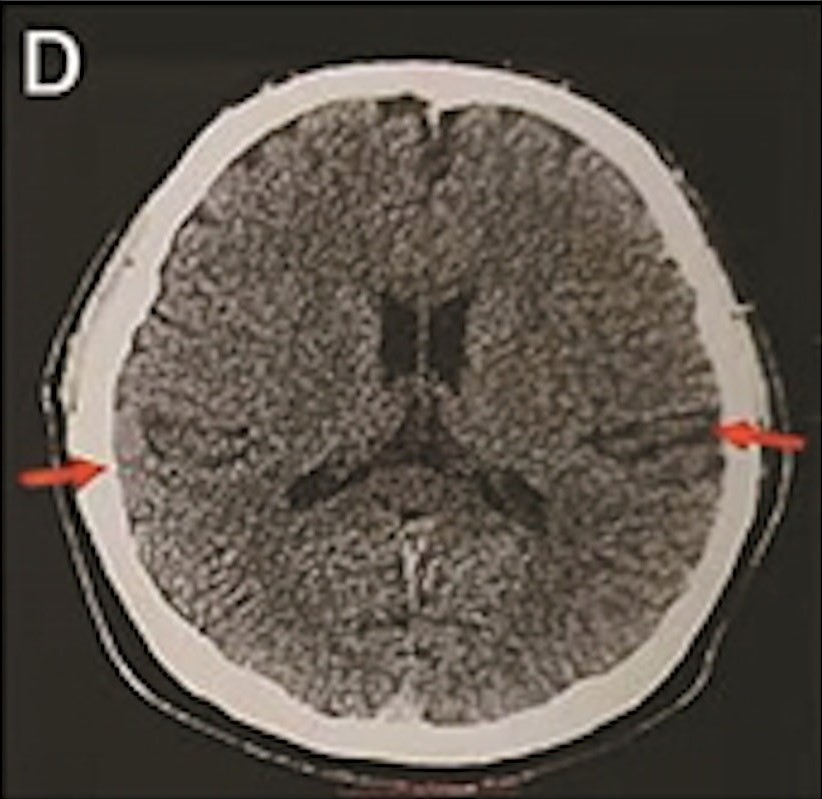

最年輕的19歲阿茲海默症男子腦部掃描結果:

19歲阿茲海默症男子腦部掃描結果(圖片來源:北京青年報)

該名19歲男子到醫院接受多項檢查,包括腦脊液指標檢測及正電子掃描。結果顯示,他出現輕度腦萎縮等症狀,最終被臨床診斷為「阿茲海默症」。